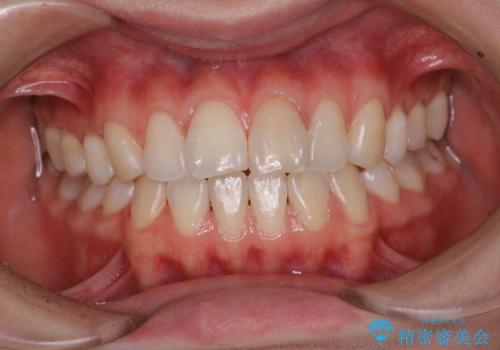

1年ぶりにPMTCで歯の着色落とし

- しばらく歯科医院へ行けなかったため、しっかり着色や汚れを落として欲しいとのことで来院されました。全体的に着色や歯石が付着していたためPMTC60分コースを行いました。

ご自身でのセルフケアだけで着色を落とそうとすると、逆に歯を傷つけてしまったり、的確に汚れを取りきれないことがあります。また、日常生活で着色しやすい飲食物を避けたりすることはストレスに感じてしまったり、あまり現実的ではありません。

定期的に歯科医院にて、適切な処置を行うことで、健康的なお口の状態を維持することにつながります。